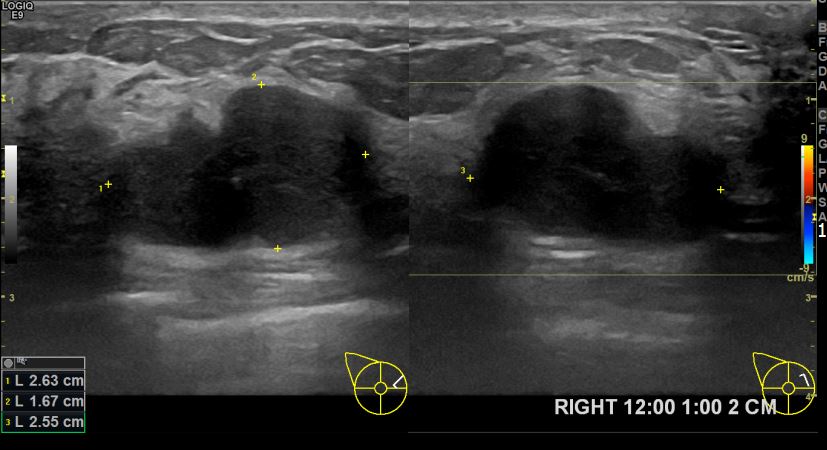

아산유외과개원후 707번째 유방암진단

상기환자 우측유방멍울만져져 내원하신 40대 여성분으로 유방암 의심혹 조직검사 시행 후 유방암 진단되었습니다.